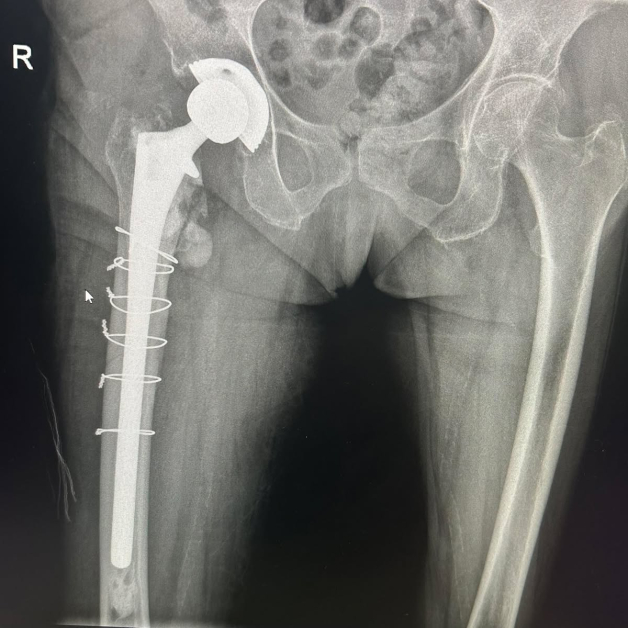

Животът на 80-годишна жена беше избавен след незабавна и сполучлива интервенция в Университетската многопрофилна болница за интензивно лекуване Каспела в Пловдив. Пациентката е с изкуствена тазобедрена става, сложена преди 7 години, само че след рухване е получила съществено строшаване на бедрената кост тъкмо под импланта.

Екипът на болничното заведение, отпред с доктор Димитър Генов и с присъединяване на доктор Благойчо Постоловски, е направил интервенцията бързо и точно. Използвано е особено ревизионно стебло, серклаж и циментна фиксация, с цел да се обезпечи непоклатимост на крайника.

Благодарение на сполучливата намеса, пациентката е могла да се изправи още на идващия ден, с отчасти натоварване на оперирания крайник – нещо извънредно значимо за възобновяване й.